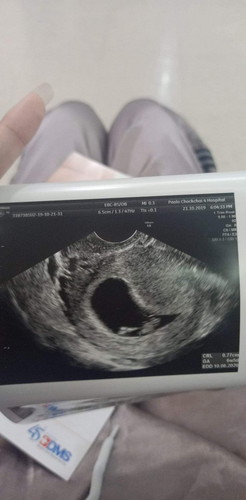

6w 3d เห็นตัวเล็กแล้ว

คุณแม่คนไหนเห็นตัวเล็กตอนกี่วีคบ้างค่ะ??